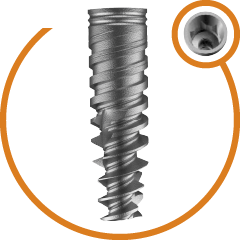

Completely Polished body of zygoma to avoid peripathogen and prevent

sinus related complication

Progressive single spiral threads. Anti- rotational cuts to improve primary stability. Higher Bone Implant contact.. More Resistance to Tensile & Compressive forces. Surface treated thread to achieve better secondary stability.

Allow insertion in minimum 1-2 drilling. Optimum Zygomatic bone engagement. Micro-polished tip without any sharp edges.